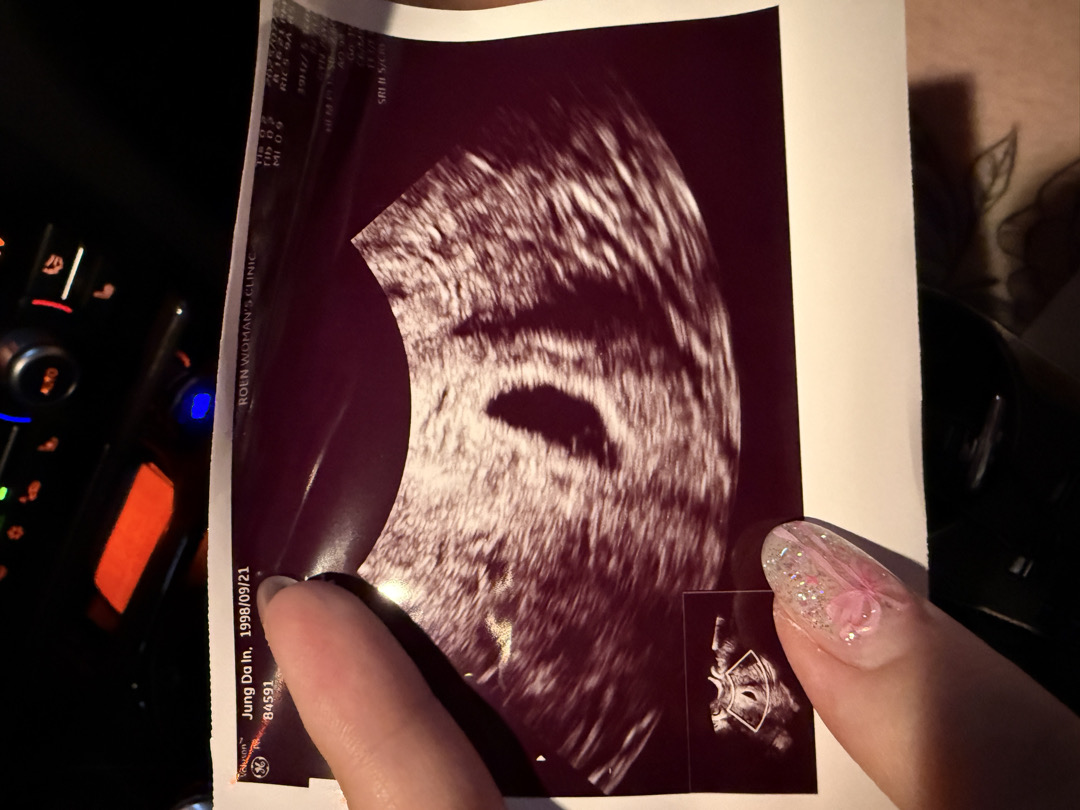

저분주에 아기집 보고 오늘 갑자기 연한핑크냉이 닦였어여 출혈은 아니였는데 한번 유산의 경험이 있어서 초음파를 보시더니 난황은 생겼는데 모양이 안좋다고 해요... 이러면 유산확률이 높다고... 이랬던 분계신가요??